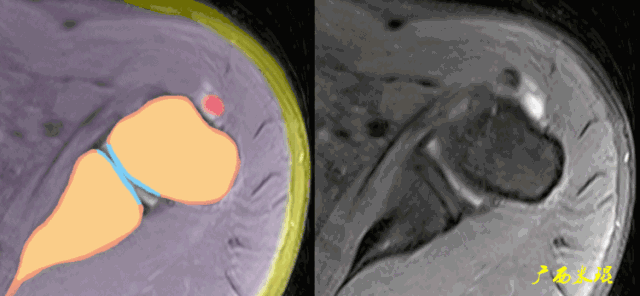

(3)肱二头肌长头腱病变

肱二头肌长头腱与肩袖关系极为密切,其肌腱炎、肌腱滑脱等改变很多情况下是伴随肩袖损伤而来的。当我们在MRI上发现肱二头肌长头腱的严重病变,应该也要考虑到有肩袖损伤的可能。

(4)肱二头肌长头腱伪影

肱二头肌长头腱有时与冈上肌因间隙而出现高信号条影,或者肱二头肌长头腱本身已经有退变信号,不仔细阅片时会误认为是冈上肌撕裂信号。